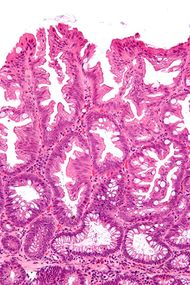

تشخص الأورام الغدية المشرشرة المفلطحة بظهورها المجهري؛ هستولوجياً، تتميز (1) بالتمدد القاعدي للخبايا، (2) تشرشر الخبايا القاعدية، (3) الخبايا الممتدة أفقياً حتى الغشاء القاعدي (الخبايا الأفقية)، و(4) تفرع الخبايا. أكثر الخصائص هذه الخصائص شيوعاً هو التمدد الجانبي للخبايا.

High magnification micrograph of a SSA showing crypt branching.